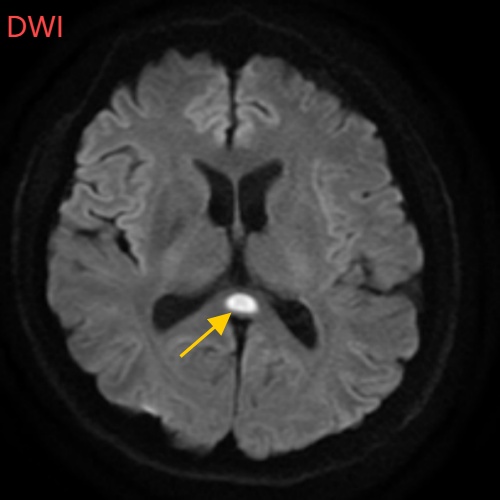

小董的影像结果显示,胼胝体压部发生病变

胼胝体压部("压部")是大脑里的"视觉总监",眼睛所看到的信息传送到大脑后,由它负责反应整合成图像在脑海中呈现。"压部"发生病变后,就像电视机信号接收不良,屏幕出现雪花一样,眼睛视物就会受到影响。除了"压部",胼胝体的其他部位也有病变,所以小董才会出现幻听、手抖等症状。